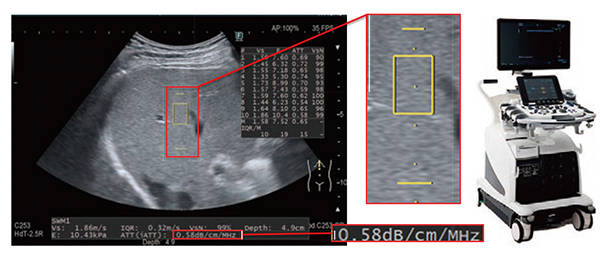

当社の超音波診断装置「ARIETTA」シリーズでは,超音波の減衰を利用した“Attenuation Measurement(以下,ATT)”を搭載し,脂肪肝評価にアプローチしている。本稿では,ATTをベーシックな処理から見直し改良した“iATT”に関して紹介する(図1)。

図1 iATTの表示と「ARIETTA 850」

減衰の推定においては,構造物なく肝臓実質を多く含めた位置で撮像することが非常に重要である。以下のガイドグラフィックと解析幅の狭域化により,WFの改善に取り組んでいる(図1)。